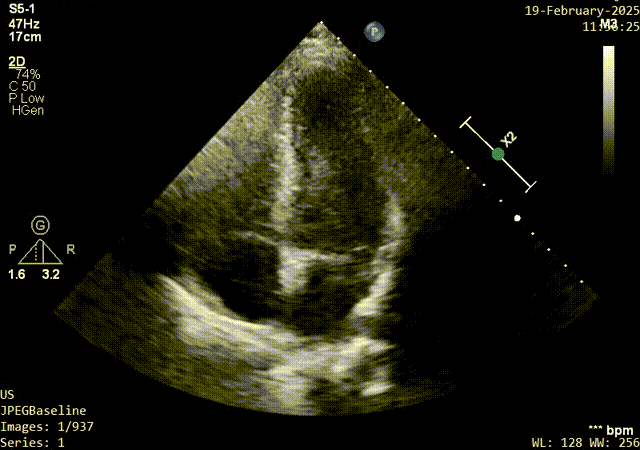

术前发泡实验超声影像

二、术前检查:右心声学造影:静息状态下,6个心动周期内左心可见造影剂微泡通过,右向左分流1级;Valsava动作(+):左心可见造影剂微泡显示,右向左分流3级。